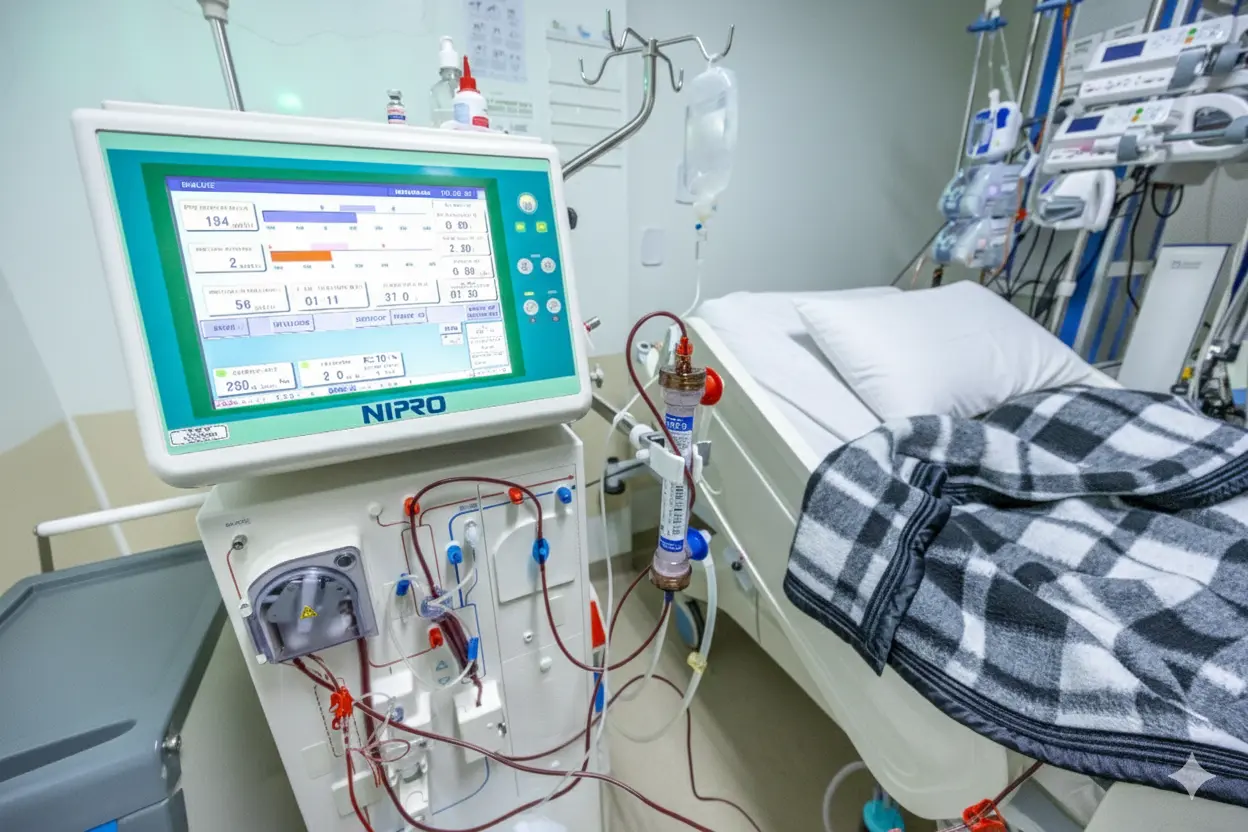

Entenda como funciona a máquina, o acesso vascular, a rotina das sessões e qualidade de vida.

Entenda em detalhes o processo de filtragem do sangue, o rim artificial e cuidados vitais.

Com a aquisição de 38 novas máquinas, hospital amplia capacidade e tecnologia para o tratamento renal.